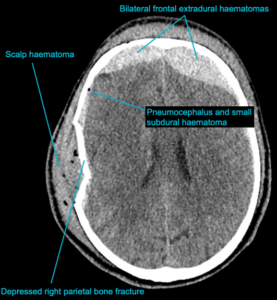

CASE 2 -A 54-year-old man walks into emergency 3 hours after a 150kg plank of wood fell on his head. He has obvious external signs of head injury and a cracking headache, however, neurologically he is intact. A CT head scan is performed

EXPLANATION –There is a depressed right parietal bone fracture with underlying pneumocephalus (indicates an open skull fracture) and a small subdural hematoma.

- Overlying this there is a scalp hematoma.

- There is also a non-displaced fracture in the frontal bone. This fracture crosses the midline and probably has injured the anterior aspect of the superior sagittal sinus.

- Tears of the dural venous sinuses may cause an extradural hematoma (EDH), as in this case. The hematoma is seen external to the compressed superior sagittal sinus.